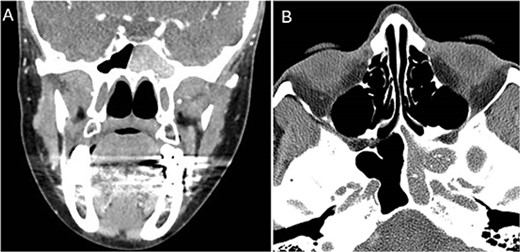

A 36 years-old man with no previous history of medical disease presented to the otolaryngology clinic with a chief complaint of headache that was associated with pressure feeling mainly in the occipital area. He also reported a post-nasal drip. The patient underwent a non-contrast paranasal sinus CT scan (Fig. 1) that demonstrated an isolated sphenoid sinus homogenous opacification, most likely representing sphenoid fungal ball. A decision was made to proceed with endoscopic sphenoidotomy (Fig. 2) to clean and remove the debris, which confirmed the diagnosis of sphenoid sinus fungal ball.

Intra-operative (A and B) endoscopic sphenoidotomy showing fungal debris, with post-operative examination (C) showing clean wide sphenoid sinus free from fungal debris.